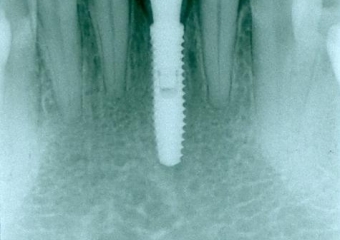

Raio x após extração e instalação do implante e dente provisório imediato